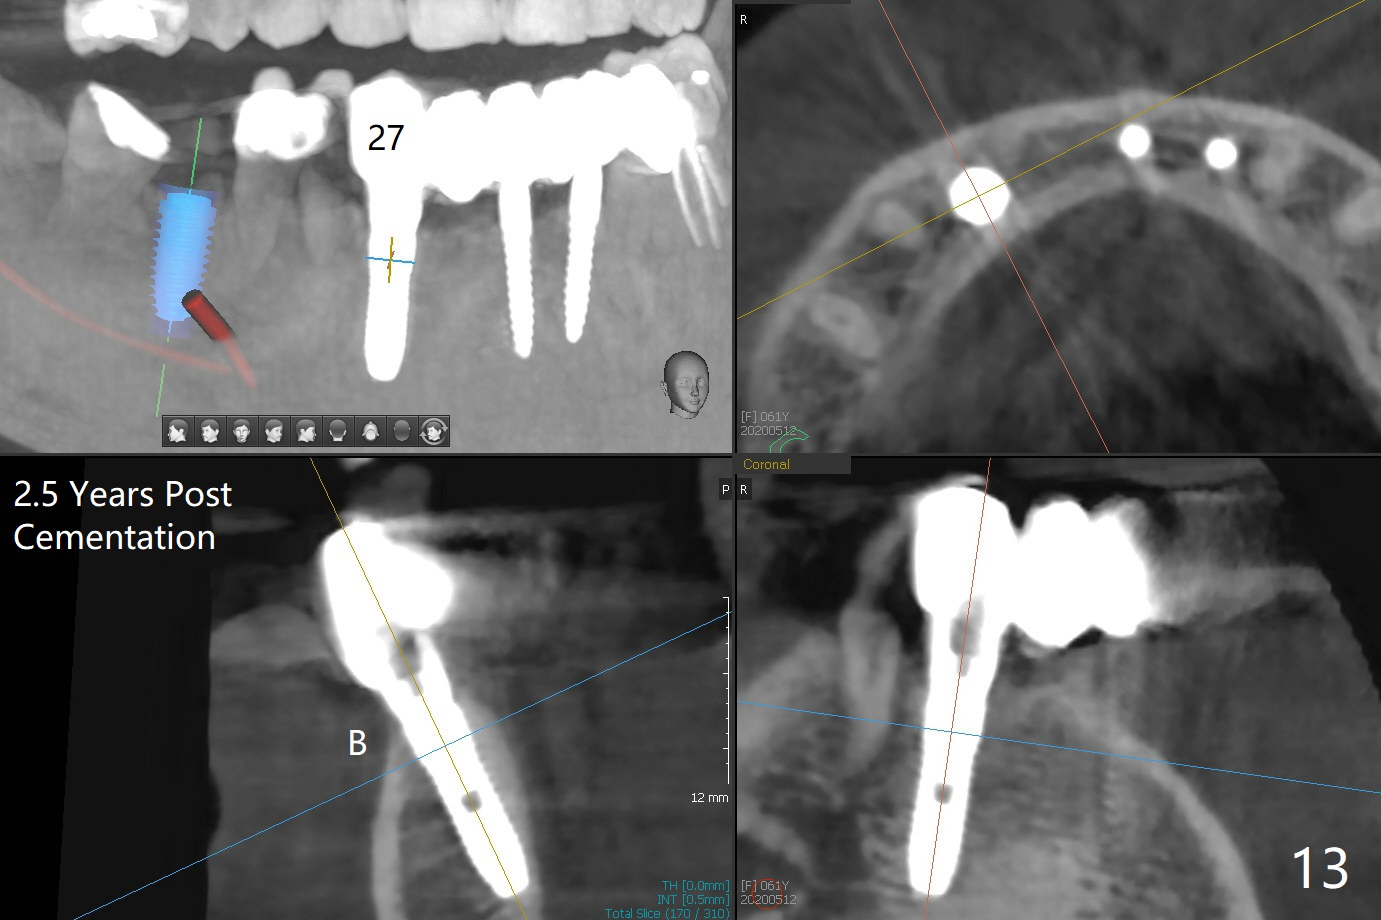

The mesial defect at #27 appears to have been repaired 8 months postop (Fig.8,9 *); there is no bone loss at 1-piece implant sites. The gingival recession seems to remain the same before and after removal of the provisional FPD (Fig.10,11). The bulging abutment at the cervix is less prominent when a straight abutment is used and prepared (Fig.12, 4.5x5.5(5) mm). There is no bone loss at #23, 25 and 27 sites 2.5 years post cementation (Fig.12-15), although the trajectory of the implants could be improved by using surgical guide (Fig.16-18).